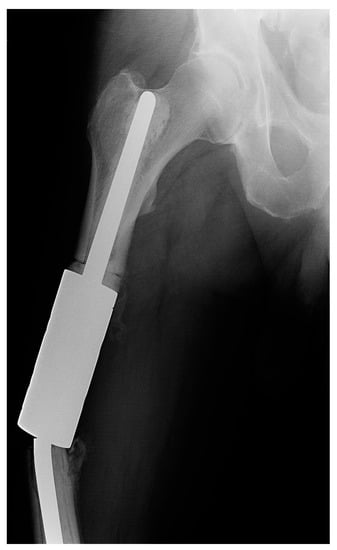

Both cases of type III failure occurred on the femur (patients 8a and 13a). Both had a fracture of the individual implant (IIIa) that occurred at the clamp-rod interface (overall, 7.4% and 11.1% of femoral reconstructions) (Figure 4). The time to failure was 4 and 8 months from the surgery and required revision with a new spacer clamp.

Figure 4.

X-ray image of a fracture at the clamp-rod interface (type III failure) of an individual femoral diaphyseal implant for renal cell carcinoma oligometastatic disease. Revision intercalary endoprosthesis was performed. This image is from patient 8 in Table 1.